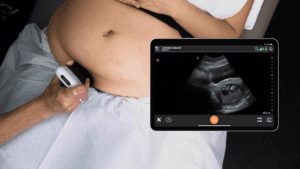

Dr. Ulrike Dehaeck, MSc, MD, FRCSC, regularly uses point-of-care ultrasound to confirm IUD localization and directly after IUD insertion to confirm placement. Last year, she switched from a bulky cart-based system to the ultra-portable Clarius wireless ultrasound system for her busy practice.

Recently, Dr. Dehaeck examined a patient to confirm IUD placement. We had the opportunity to record a 60-second video tutorial of the pelvic exam using the Clarius C3 HD3 in which she demonstrates where to place the scanner for sagittal and transverse views of an IUD in position. Watch the video to see her technique.